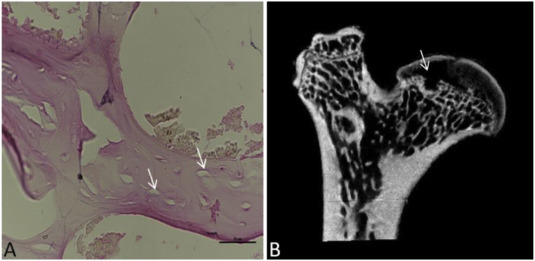

结果:创伤性ONFH模型成功与否的评估:由于感染,模型组的四个右股骨被排除。 Micro-CT和H&E染色是评估创伤性ONFH模型成功与否的有效方法。用这两种方法对模型组所有右股骨进行分析。显微CT表现为软骨下骨组织小梁连续性中断、紊乱,局部小梁稀疏、薄。此外,H&E染色结果也显示了ONFH的典型特征,其中出现了许多空腔。

图3、模型组H&E染色及micro-CT评价:(A)40倍放大下H&E染色股骨头冠状面图像。黑色箭头表示空腔,小梁紊乱,局部小梁稀疏、薄。(B) 股骨头冠状面显微CT扫描图像。白色箭头表示骨密度降低,多孔性增加,小梁连续性中断、紊乱和变薄。